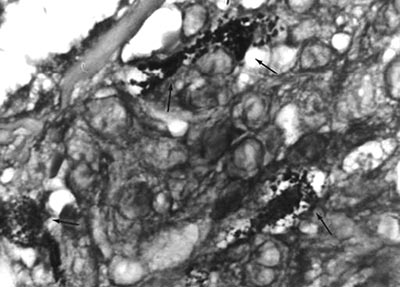

TB-Mykobakterien sind bekanntermaßen „pleomorph“, sie können also in Kulturen und im Gewebe verschiedene Wachstumsformen aufweisen. Seit Jahrzehnten schon untersucht man „pleomorphe“ Formen von M. tuberculosis und anderen Spezies von „nichttuberkulösen“ und „atypischen Mykobakterien“ hinsichtlich ihrer Auswirkungen auf menschliche Krankheiten. Leider schenken die Wissenschaftler diesen pleomorphen Formen wenig Aufmerksamkeit, und Pathologen stützen sich in erster Linie auf den Nachweis „typischer“ säurefester Stäbchenformen von Mykobakterien, um Tuberkulose und/oder mykobakterielle Krankheiten zu diagnostizieren (Abb. 4). Das ist bedauerlich, weil die säurefesten Bakterien, die bei AIDS und Krebs (und einigen anderen immunologischen Krankheiten) nachgewiesen werden können, meist pleomorphe und „filterbare“ Formen sind, die oft unerkannt bleiben (Abb. 1 bis 3).

Abb. 1: Pleomorphe Bakterien in einem vergrößerten Lymphknoten eines frühen AIDS-Stadiums. Zu sehen sind sowohl große Russell-Körperchen (RB) als auch kleine, runde, kokkenartige Formen (Pfeil). Gram-Färbung, tausendfache Vergrößerung, in Öl.

Abb. 2: Winzige gekörnte und kokkenartige Formen von Bakterien (Pfeile) im Hauttumor eines AIDS-bedingten Kaposi-Sarkoms. Säurefeste Färbung, tausendfache Vergrößerung, in Öl.

Abb. 3: Drei Gebiete von violett gefärbten, runden, kokkenartigen Bakterienformen in einem Fall von AIDS-bedingtem Kaposi-Sarkom der Haut. Säurefeste Färbung, tausendfache Vergrößerung, in Öl.